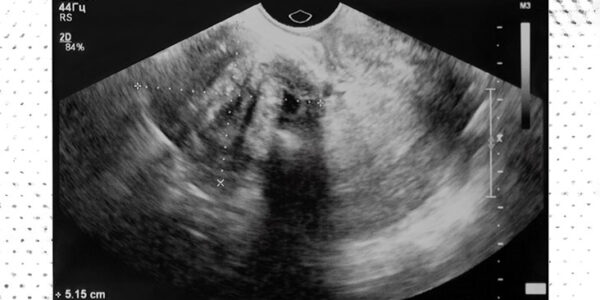

¿Qué es la embolización de la arteria uterina?

La embolización de la arteria uterina es un procedimiento mínimamente invasivo. Bloquea el flujo de sangre a los tumores no cancerosos llamados fibromas en el útero, lo que hace que se encojan y mueran. Los fibromas uterinos son crecimientos que…